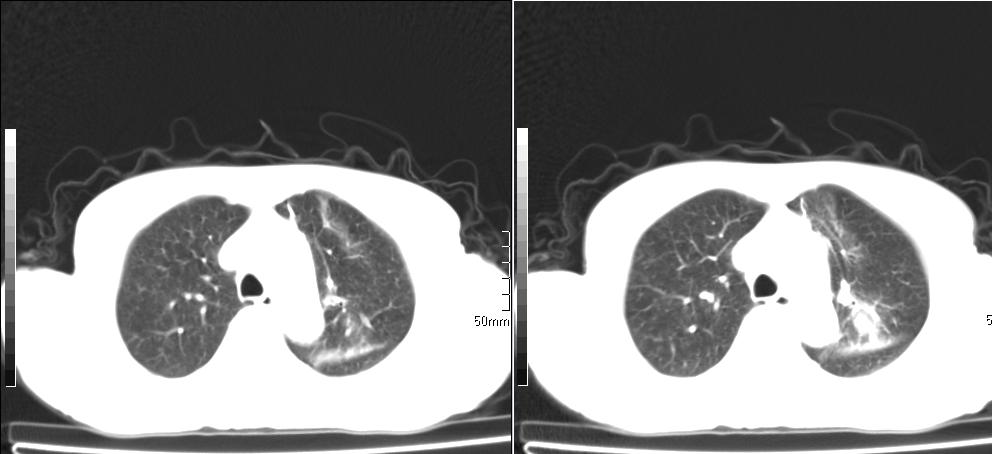

标题: CT26857:女,60岁,胃部不适前来就诊,不咳嗽,乏力,胸椎 [打印本页]

标题: CT26857:女,60岁,胃部不适前来就诊,不咳嗽,乏力,胸椎

1、胸椎有骨质破坏伴周软组织,考虑胸椎转移。2、考虑左肺上叶尖后段支气管开口区周围型肺癌可能。

1、胸椎有骨质破坏伴周软组织,考虑胸椎转移。2、考虑左肺中央型肺癌可能。

1)考虑左肺中央型肺癌。2)胸椎转移瘤不排除;建议行mri检查。